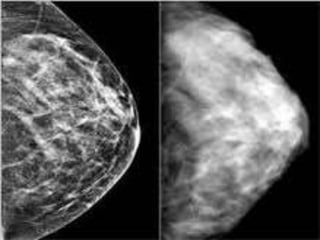

Durante os exames radiográficos das mamas, realiza-se as

incidências mamográficas mais comuns crânio caudal

(CC) e médio lateral oblíqua (MLO).